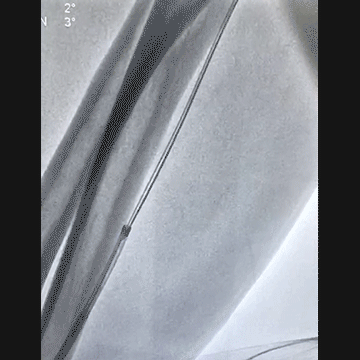

穿刺导丝掉进桡动脉,已经完全出了动脉鞘外。

先是从桡动脉鞘进抓捕器没有抓捕成功,后来从股动脉进抓捕器也没有抓捕成功。

桡动脉鞘进JR 4.0指引导管,送入Sion,沿Sion送入2.5mm球囊,球囊越过穿刺导丝到达远端,6atm“打起来”后回撤,导丝被球囊带回来到指引导管口附近。